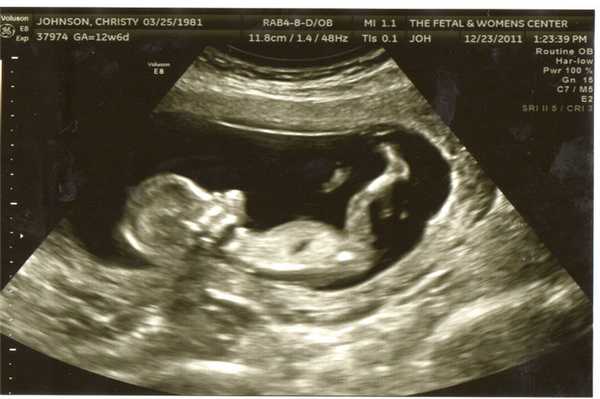

Фото УЗИ ребенка на разных сроках беременности

Если беременность желанная, будущие родители внимательно относятся к пренатальной диагностике плода. Чтобы убедится, что ребенок развивается нормально, в течение 9 месяцев гинеколог несколько раз направляет женщину на ультразвуковое исследование. Фото УЗИ может многое рассказать врачу и будущим родителям о малыше. Кроме того, снимок станет трогательным напоминанием для семейного архива.

Чтобы сделать фото УЗИ малыша на разных сроках, беременной женщине необходимо записаться на ультразвуковой скрининг в медицинском центре «Диана».

Фото УЗИ ребенка на 12 неделе беременности

Это очень важный период, поскольку гинеколог направляет женщину на первый скрининг. Он включает УЗИ и биохимический анализ венозной крови на гормоны. Ультразвуковое исследование в это время очень информативно и позволяет определить ряд врожденных патологий.

Визуально на фото видны такие особенности плода:

- хорошо просматриваются глаза (они обычно закрыты), нос малыша и другие черты лица;

- ребенок может открывать рот и глотать околоплодные воды;

- размеры плода все еще непропорциональны, но все части тела сформированы;

- в области половых органов происходит гипотрофия мошонки у мальчиков или гипертрофия половых губ у девочек (по этим признакам можно определить пол);

- движения плода хаотичные.

Скрининг на 12 неделе позволяет определить ряд патологий внутриутробного развития. Для этого аппарат УЗИ проводит ряд автоматизированных замеров. На основе этих измерений производят оценку формирования плода.

В этот период обязательно определяют такие параметры:

- длина плода;

- длина бедра;

- окружность живота;

- обхват головы;

- копчико-теменной размер (КТР) - длина от темечка до копчика;

- бипариетальный размер (БПР) - размер от одного виска до другого;

- толщина воротникового пространства;

- объем грудной клетки;

- вес плода (рассчитывается исходя из замеров).

Сопоставить эти данные и выявить патологию может только врач. Если специалист подозревает врожденное заболевание, назначают дополнительный хромосомный анализ.